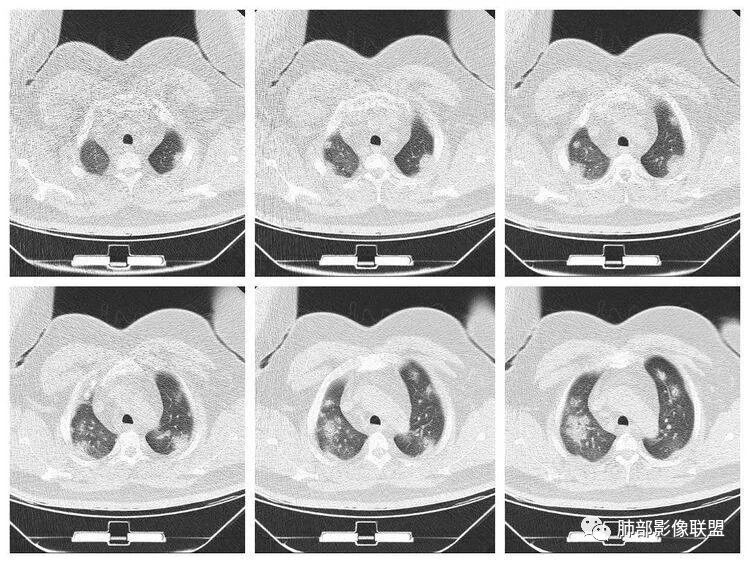

青年男性、急性病史、发热、咳嗽、常规抗炎无效病灶沿支气管血管束分布  GGO+实变边界模糊部分沿胸膜下分布哪几种可能?

南边:1、感染:间质分布——病毒、支原体,支原体一般树芽征明显,累及小气道多,而且临床轻,不太支持2、血管炎,需要相关病史3、肺水肿:心脏不大,无胸水、无中央间质增厚、小叶间隔增厚,不太支持4、PAP,病史影像表现都不支持初学者:可能是病毒,但是好像并不是我们常见的流感病毒实变为主,腺病毒?就是太多灶了一点

重症流感的定义出现以下情况之一者为重症病例1.持续高热>3天,伴有剧烈咳嗽,咳脓痰、血痰,或胸痛2.呼吸频率快,呼吸困难,口唇紫绀;3.神志改変:反应迟钝、嗜睡、躁动、惊厥等4.严重呕吐、腹泻,出现脱水表现;5.合并肺炎6.原有基础疾病明显加重。危重症流感的定义出现以下情况之一者为危重病例1.呼吸衰竭2.急性坏死性脑病3.脓毒性休克4.多脏器功能不全5.出现其他需进行监护治疗的严重临床情况。重症流感病毒肺炎的肺部影像以双肺多发磨玻璃影及实变影为主要表现,可合并少量胸腔积液,典型的H1N1双肺外带分布为主。随病程发展,部分患者出现实变及纤维化临床表现早期流感样症状:咳嗽、咳痰、发热、咽痛、全身酸痛。主要临床表现:肺炎、ARDS。患者咳嗽、咳痰、呼吸困难、氧饱和度低,发热、咽痛、全身酸痛,神志异常。甚至呼吸衰竭、休克,多器官衰竭等等。相关链接https://m.qlchat.com/topic/details?topicId=280000451285864

起病突然,高热,双肺多发磨玻璃影及实变影,胸膜下分布为主,不具有肺门分布优势,也没有小叶间隔增厚,一般会首先考虑病毒感染,尤其是甲流。